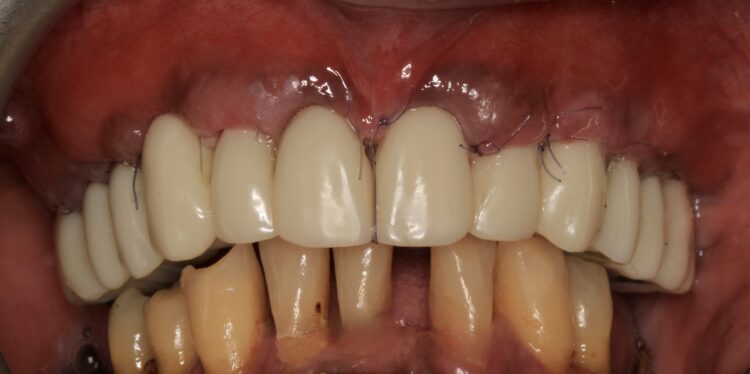

The finished and polished provisional restoration was screwed on the multiunit abutments at 15Ncm. The buccal flap was coronally advanced and closed with sling sutures using resorbable monofilament Glycolon 5/0 sutures.

This phase of treatment concluded with radiographs to confirm accurate implant placement. The patient was also given standard post-operative oral hygiene and care instructions. He reported no complications or concerns during the review appointment a week later.

After the follow up appointments at one and four weeks, the patient was scheduled for periodic maintenance every three months. The retrievability of the final screw-retained zirconia-titanium supported prosthesis allowed management of the interface over time. At the one-year review, further growth and maturation of the soft tissue as well as the health of the keratinised peri-implant tissues were evident, without signs of bleeding on probing.